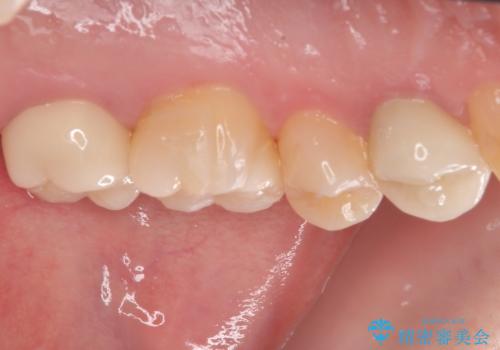

- 奥歯に物が挟まるとのことで来院された患者様です。

レントゲン写真より、奥歯2本に大きなむし歯があることが分かりました。

手前の歯はセラミックインレーで、奥の歯はオールセラミッククラウンにて治療を行うこととしました。

むし歯の範囲は大きかったですが、事前の症状もなく、処置後も一切の痛みなく快適に過ごすことができています。